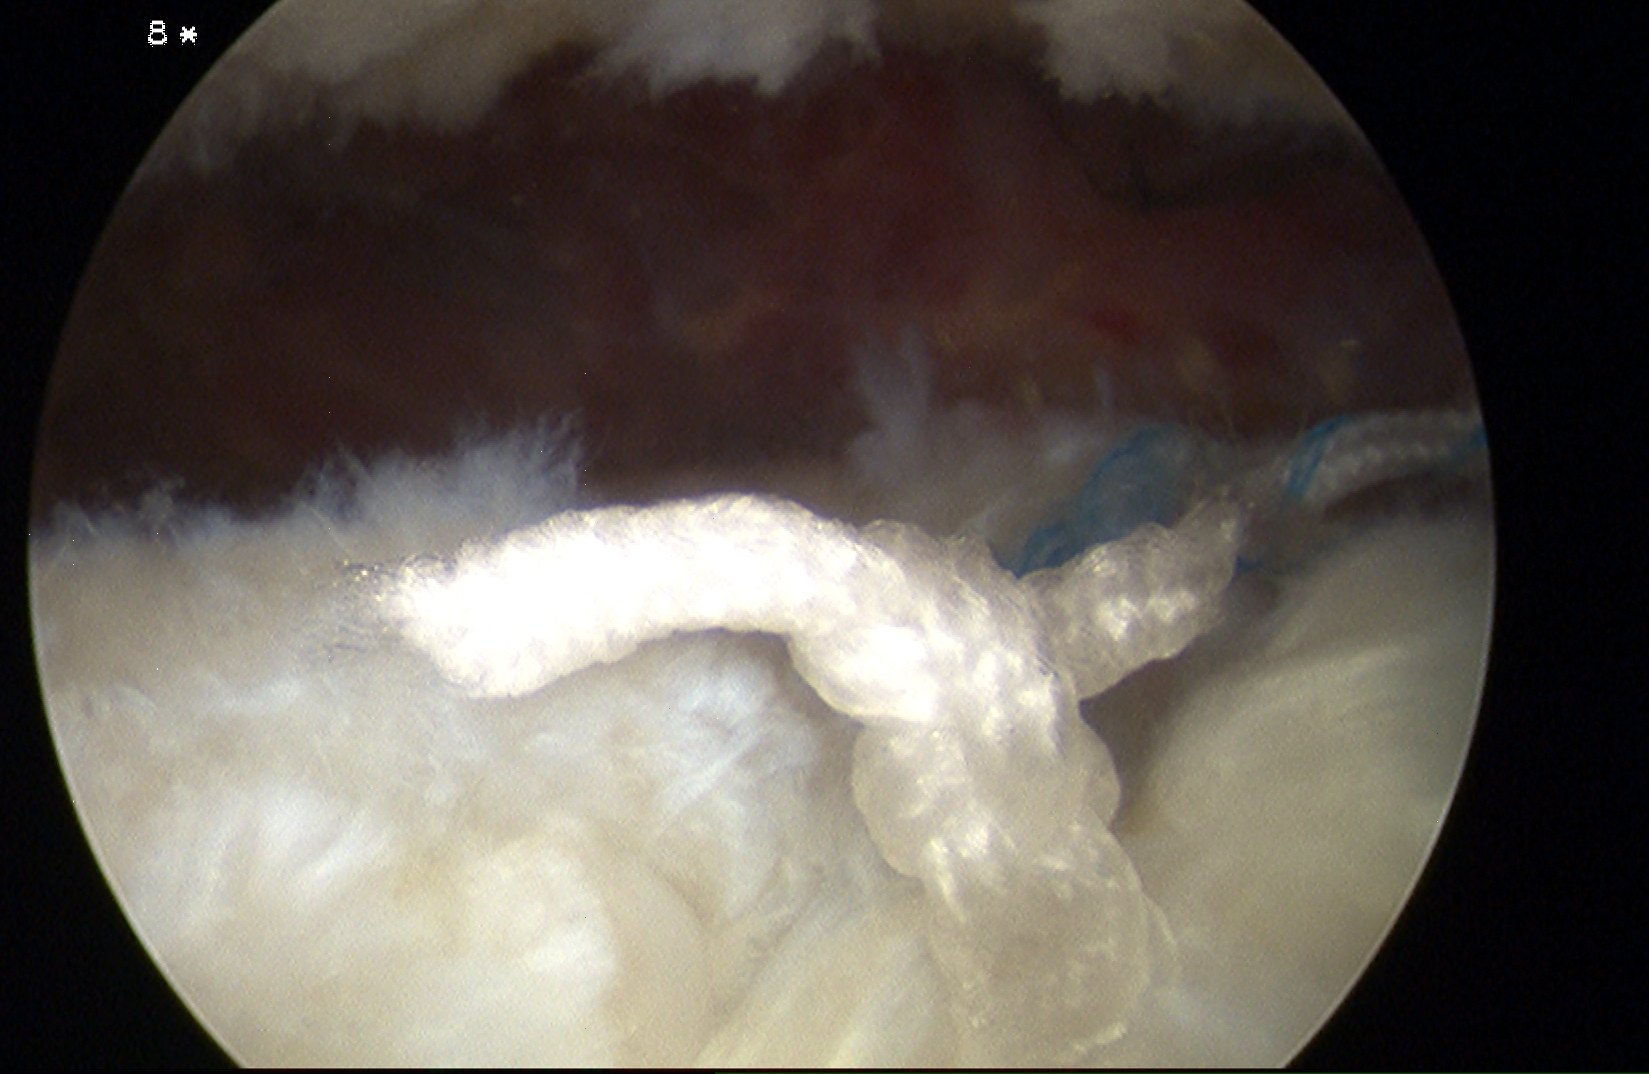

Bursal Sided

> 50% bursal sided tears with camer in subacromial space